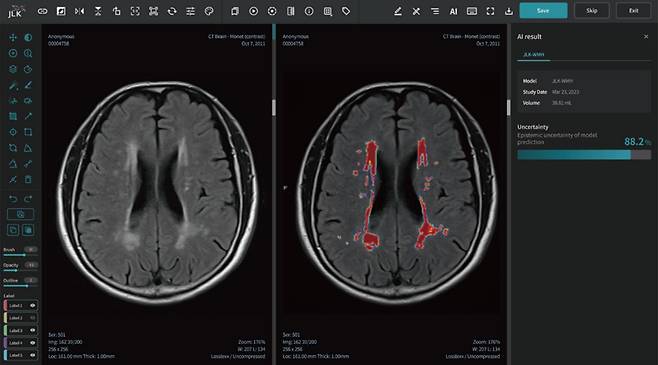

의료 인공지능(AI) 1호 상장기업 제이엘케이는 대뇌 백질 변성분석 AI 솔루션(JLK-WMH)의 급성 뇌졸중 환자 대상 뇌백질변성 정량 분석 연구 결과가 국제 학술지에 출판됐다고 22일 밝혔다.

이 논문에는 급성 뇌졸중 환자 8421명의 MRI 데이터를 AI에 학습시켜 만성 뇌 허혈 병변에 해당하는 백질 변성(WMH) 영역을 시각화하고 정량적으로 분석하는 'JLK-WMH'의 개발 과정과 성능 연구 등이 담겼다.

의료 인공지능(AI) 1호 상장기업 제이엘케이는 대뇌 백질 변성분석 AI 솔루션(JLK-WMH)의 급성 뇌졸중 환자 대상 뇌백질변성 정량 분석 연구 결과가 국제 학술지에 출판됐다고 22일 밝혔다. 이 논문에는 급성 뇌졸중 환자 8421명의 MRI 데이터를 AI에 학습시켜 만성 뇌 허혈 병변에 해당하는 백질 변성(WMH) 영역을 시각화하고 정량적으로 분석하는 'JLK-WMH'의 개발 과정과 성능 연구 등이 담겼다.

논문에 따르면 제이엘케이 AI 솔루션은 급성 뇌졸중 환자의 MRI 영상을 분석해 환자의 백질 변성 영역을 빠르고 정확하게 탐지하고 정량했다. 10년 이상의 경력을 보유한 전문의와의 정량 분석 일치도가 99%에 달했다. 제이엘케이는 치매 등 퇴행성질환의 조기 진단 및 연구에 널리 활용될 수 있을 것으로 기대했다.